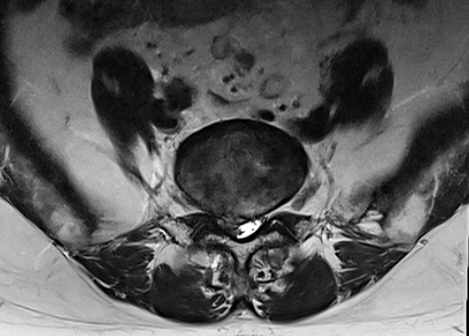

L4/L5レベル 腰椎すべり症

L5/S1レベル 椎間板ヘルニア・右背側に突出